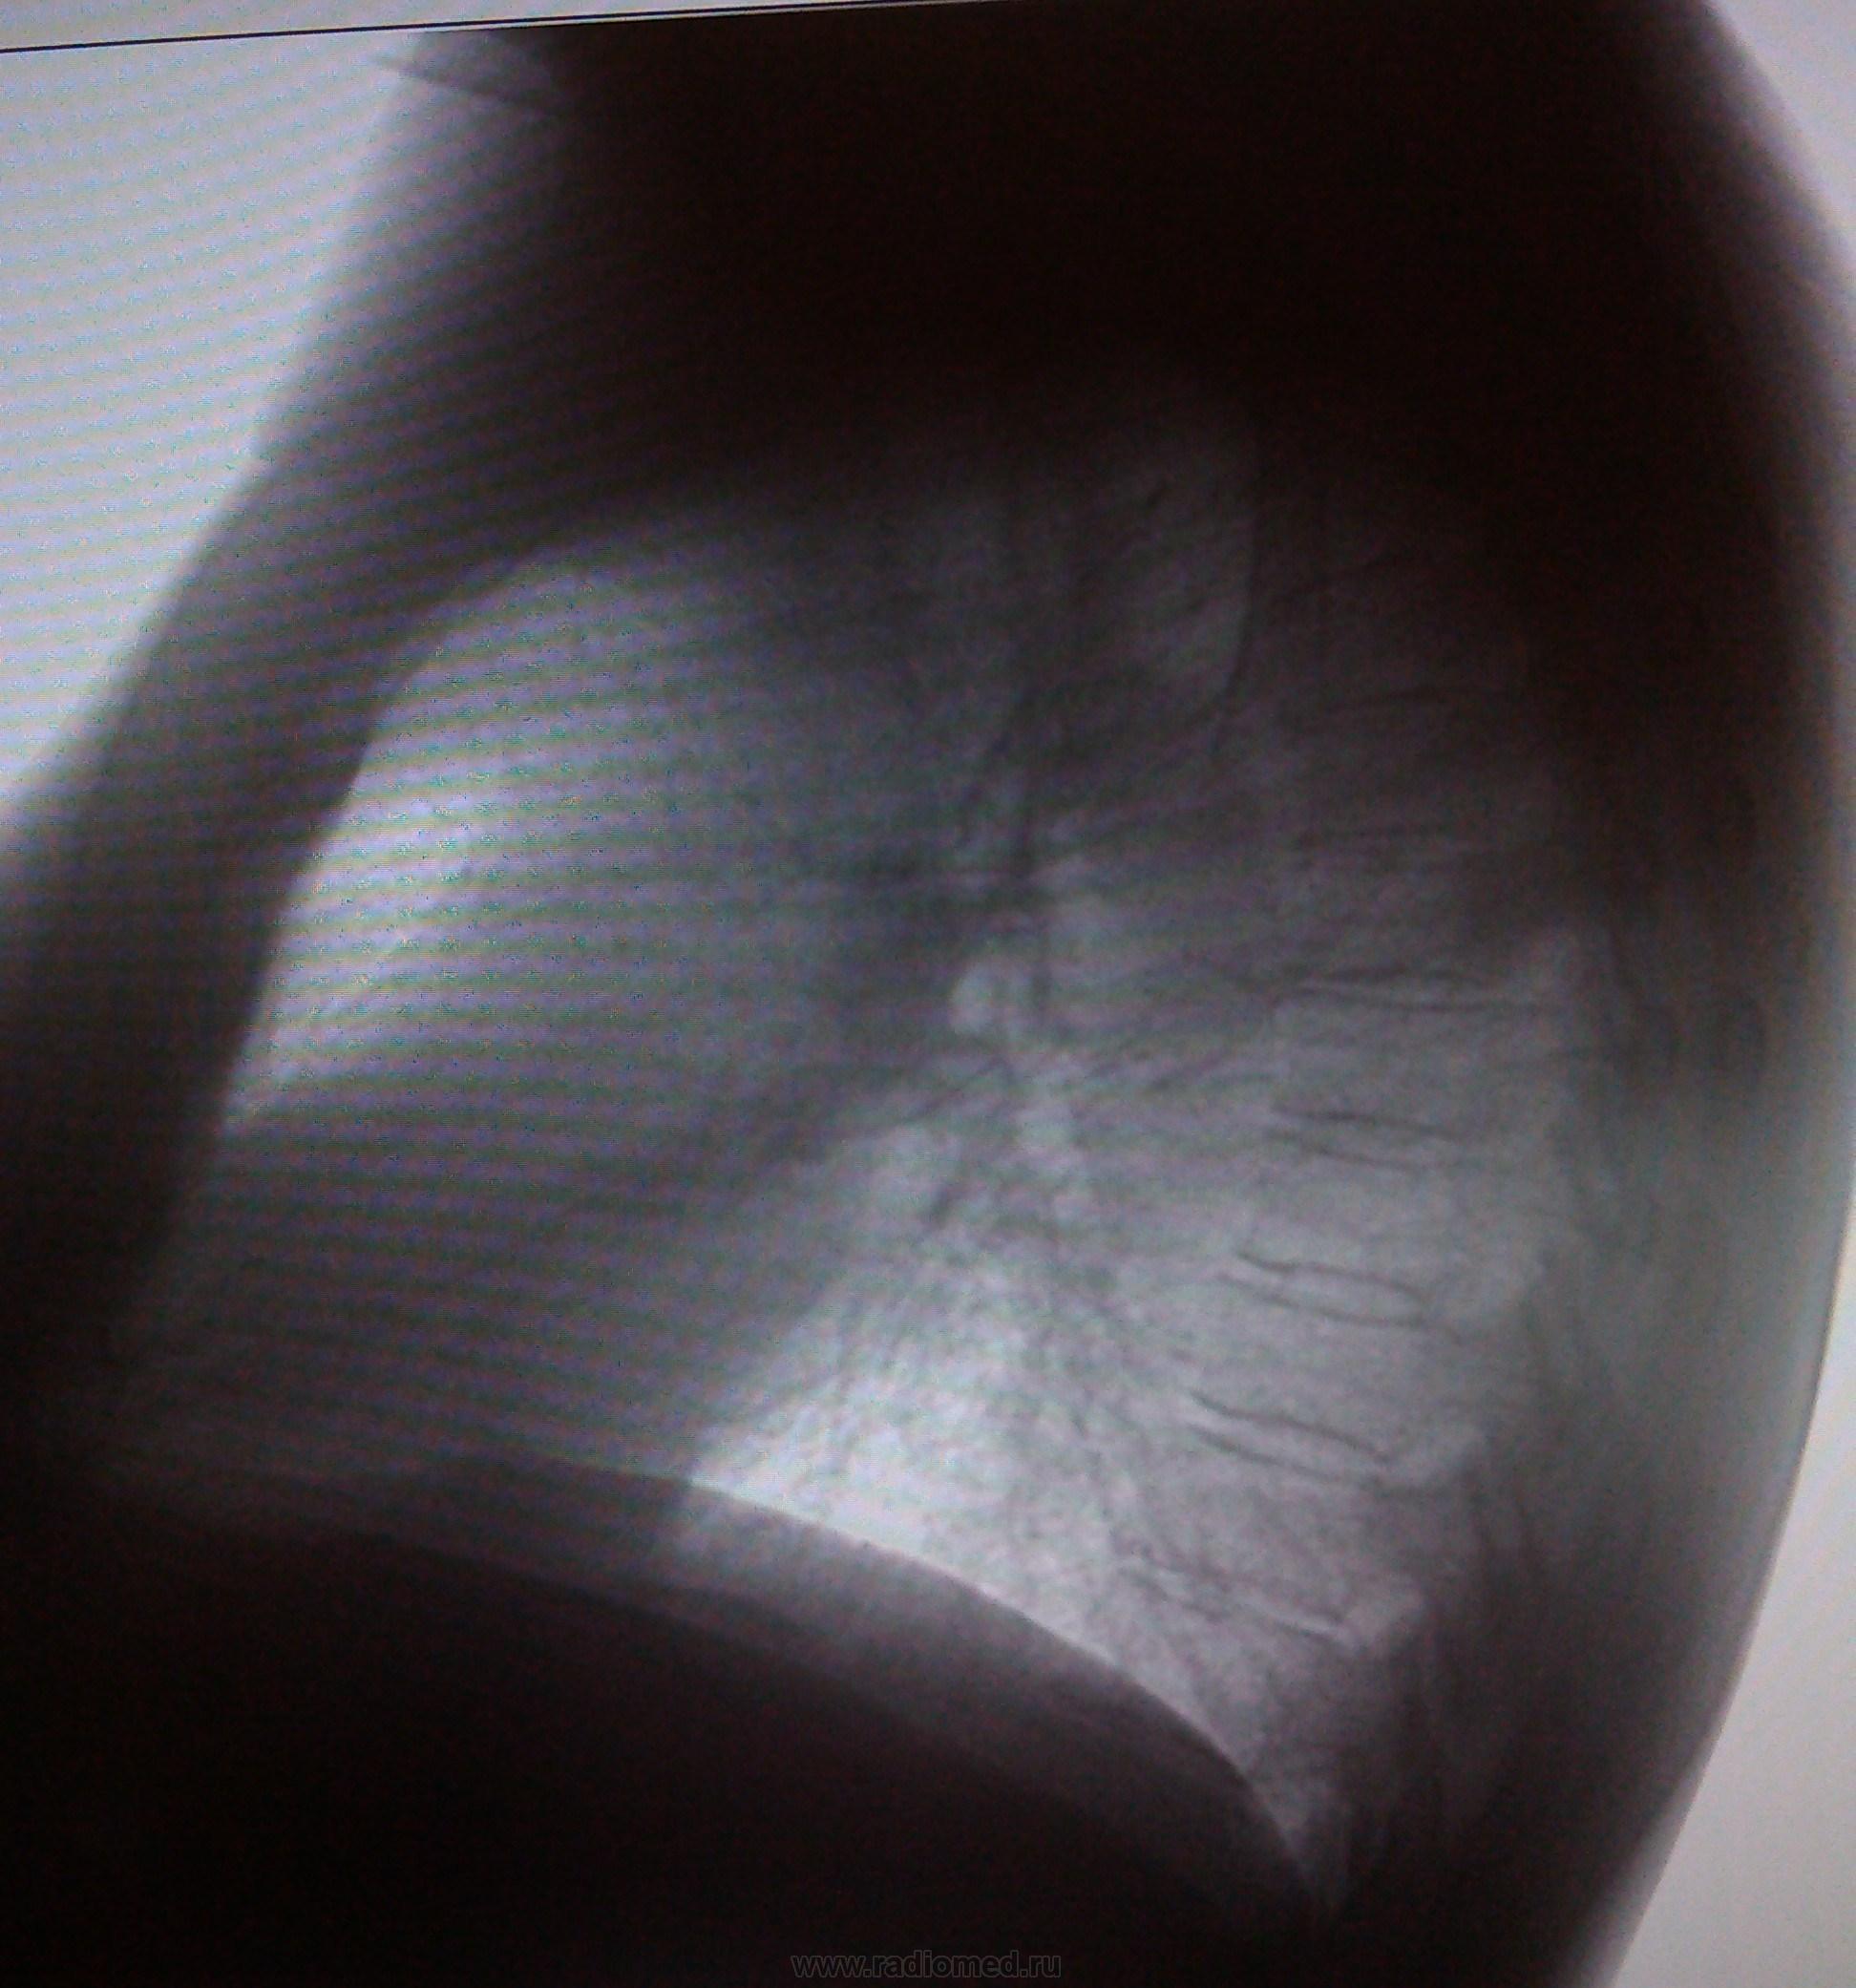

Пол пациента: Женский пол Тип патологии: Другое Область исследования: Скелетно-мышечная система Методы исследования: Другие Пациентка, 64 года. Ежегодное обследование. 2012 г. 2013 г. https://radiomed.ru/sites/default/files/styles/case_slider_image/public/user/18609/img_20130806_150906.jpg?itok=YYBrO0Hv https://radiomed.ru/sites/default/files/styles/case_slider_image/public/user/18609/img_20130806_150935.jpg?itok=Q0UbHUzS https://radiomed.ru/sites/default/files/styles/case_slider_image/public/user/18609/img_20130806_150948.jpg?itok=q6EktgXQ ID:30480 Втр, 06/08/2013 - 21:46 #1 Сергей Кузьминов Не на сайте Был на сайте: 1 год 1 неделя назад Зарегистрирован: 06.10.2012 - 15:51 Публикации: 11813 ИМХО растет рачёк в средней доле справа. Втр, 06/08/2013 - 22:12 #2 Андрей Юрьевич Не на сайте Был на сайте: 1 день 21 час назад Зарегистрирован: 16.11.2008 - 22:16 Публикации: 18098 Рак-не рак (может оказаться фиброзом), но дообследовать надо. Если ранее не обследовалась. Андрей Юрьевич Втр, 06/08/2013 - 22:51 #3 Dr. X-ray Не на сайте Был на сайте: 9 лет 6 месяцев назад Зарегистрирован: 19.07.2013 - 21:06 Публикации: 505 КТ? Ср, 07/08/2013 - 06:32 #4 Андрей Юрьевич Не на сайте Был на сайте: 1 день 21 час назад Зарегистрирован: 16.11.2008 - 22:16 Публикации: 18098 Если доступно, то да. Например, одному пациенту из Орловской области, делать КТ пришлось в Москве. Оказалось, так проще. Андрей Юрьевич Ср, 07/08/2013 - 10:36 #5 медсанчасть рег... Не на сайте Был на сайте: 11 лет 1 месяц назад Зарегистрирован: 11.06.2013 - 10:46 Публикации: 136 Диф.диагноз онко и туб.процесс. Пт, 09/08/2013 - 15:36 #6 оксана анатольевна Не на сайте Был на сайте: 10 лет 3 недели назад Зарегистрирован: 31.10.2012 - 22:33 Публикации: 29 туберкулез не исключается. Но может быть и онкология .

ИМХО растет рачёк в средней доле справа.

Рак-не рак (может оказаться фиброзом), но дообследовать надо. Если ранее не обследовалась.

Диф.диагноз онко и туб.процесс.

туберкулез не исключается. Но может быть и онкология .